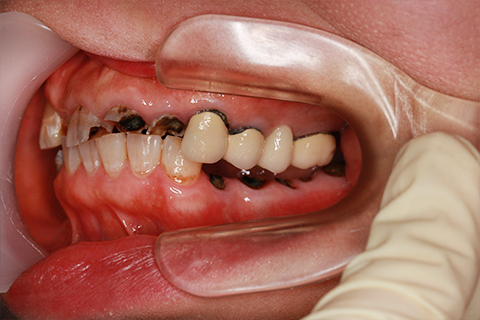

症例4

- 年齢・性別

- 60歳

- 治療期間

- 6ヶ月

- 抜歯

- 残根抜歯のみ

- 治療費

- 198万円

- 備考

- 右上5.6 右下5 左下4.5.6欠損

- 治療内容

- 6本のインプラントを右左側に2回に分けて埋入

- 施術の副作用(リスク)

- オペによる知覚障害。インプラントによる歯肉炎。インプラント脱落。